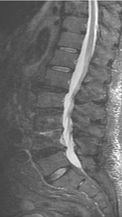

Спондилодисцит L3 – L4

4 процедуры ФДТ, 9 процедур MBST, 20 процедур ИПМТ

Параметры изменяются в зависимости от процедуры

Дата публикации: 22.08.2025 14:27:12